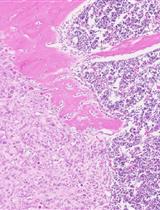

Bone metastasis is a frequent and lethal complication of many cancer types (i.e., prostate cancer, breast cancer, and multiple myeloma), and a cure for bone metastasis remains elusive. To recapitulate the process of bone metastasis and understand how cancer cells metastasize to bone, intracardiac injection and intracaudal arterial animal models were developed. The intratibial injection animal model was established to investigate the communication between cancer cells and the bone microenvironment and to mimic the setting of prostate cancer patients with bone metastasis. Given that detailed protocols of intratibial injection and its quantitative analysis are still insufficient, in this protocol, we provide hands-on procedures for how to prepare cells, perform the tibial injection, monitor tibial tumor growth, and quantitatively evaluate the tibial tumors in pathological samples. This manuscript provides a ready-to-use experimental protocol for investigating cancer cell behaviors in bone and developing novel therapeutic strategies for bone metastatic cancer patients.